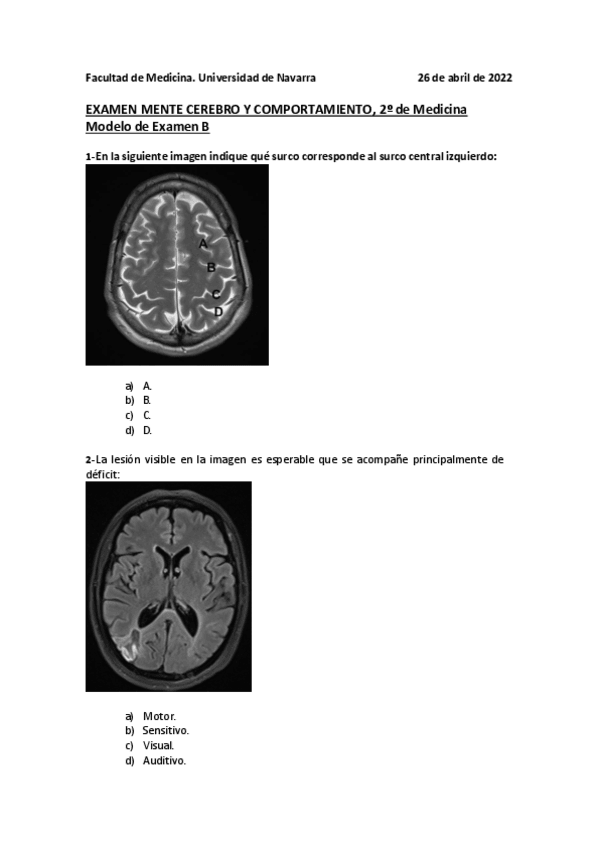

He publicado nuevos apuntes de 2º Mente, cerebro y comportamiento: MCC-PARCIAL-26-ABRIL-2022-CON-RESPUESTAS-2.pdf

15 páginas